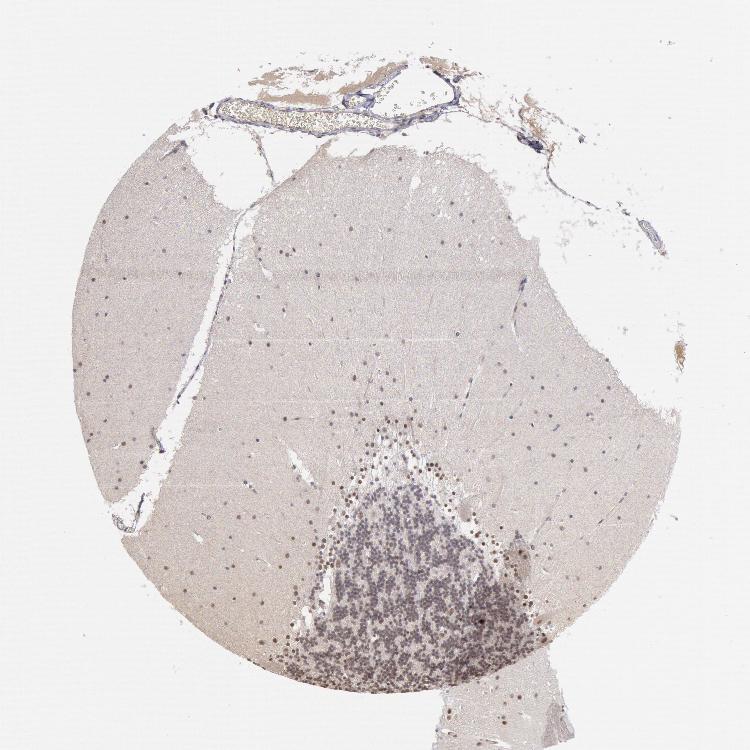

BRAIN CEREBELLUM Show tissue menu

CEREBELLUM - Expression summary

Protein expression

Cerebellumi

On the top, protein expression in current human tissue, based on all annotated cell types, is reported with the units not detected (n), low (l), medium (m) and high (h). Underneath, protein expression in each annotated cell type are reported using the same units.

Protein expression data is based on knowledge-based annotation. For genes where more than one antibody has been used, a collective score is set.

If knowledge-based annotation could not be performed for a gene, no data is displayed here. View antibody staining data further down this page.

h

m

l

n

Cells in granular layer: Not detected

Cells in molecular layer: Medium

Purkinje cells: Low

CEREBELLUM - Antibody stainingi

Antibody staining in the annotated cell types in the current human tissue is reported as not detected, low, medium, or high, based on conventional immunohistochemistry profiling in selected tissues. This score is based on the combination of the staining intensity and fraction of stained cells.

Each image is clickable and will lead to virtual microscopy that enables deeper exploration of all samples and also displays staining intensity scores, fraction scores and subcellular localization as well as patient and tissue information for each sample.

Antibody HPA001233Antibody CAB017185

Purkinje cells LowHigh

Cells in granular layer Not detectedMedium

Cells in molecular layer MediumHigh